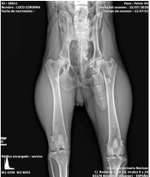

Hallo liebes Team, unser oeb rüde (2 1/2 Jahre) hat seit über 3 Wochen jetzt mit starkem Durchfall zu tun. Die ersten Tage kot wie Wasser u erbrechen selbst nach dem saufen>Tierarzt, hohe blutWerte, Infusion, röntgen, Antibiotika für 5 Tage. 2 Tage nach Antibiotika Ende wieder Durchfall, abends nur ...